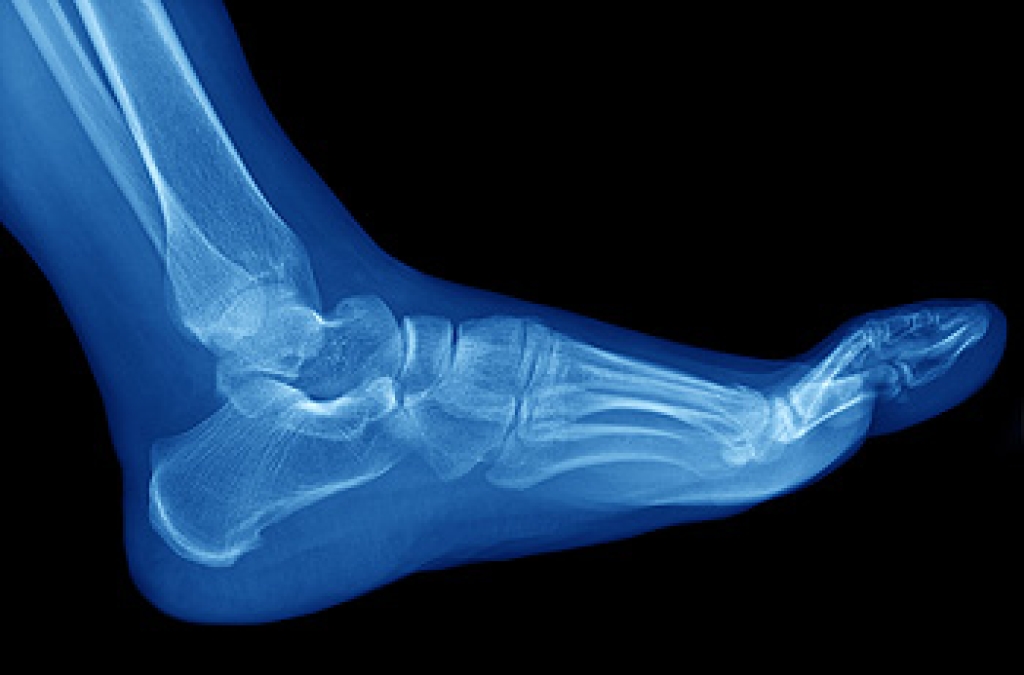

Diagnosis

Due to the wide variety of potential causes of ankle pain, podiatrists will utilize a number of different methods to properly diagnose ankle pain. This can include asking for personal and family medical histories and of any recent injuries. Further diagnosis may include sensation tests, a physical examination, and potentially x-rays or other imaging tests.